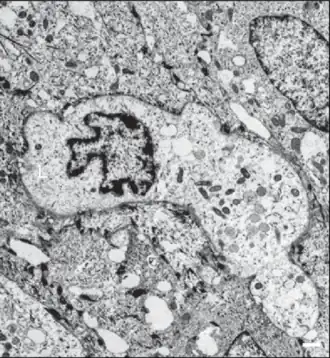

Ultraestructura

Con microscopía electrónica las LC son células de aspecto estrellado, sus finas prolongaciones («dendritas») atraviesan las uniones estrechas hacia el estrato córneo y pueden buscar antígenos en varias capas de la epidermis.[6]

El núcleo es dentado con circunvoluciones o bien lobulado.

El citoplasma es electrolúcido, desprovisto de tonofilamentos y melanosomas.[9]

Inicialmente se identificaron por un marcador citoplasmático específico, el gránulo de Birbeck, un orgánulo denso en electrones.

La célula CL muestra ausencia de desmosomas.[9]